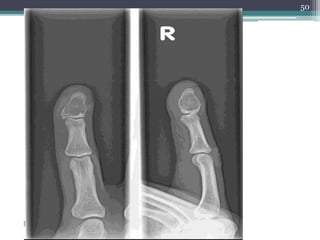

CLINICAL FEATURES

• Symptomatic,

• Painful mass,

• Pathologic fracture,

• X-RAYS: O-ring sign (well demarcated

radiolucent lesions ).

• MAFFUCCI SYNDROME: risk of developing

other malignancies